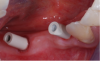

Fig 7. Scan bodies in place.

Figure 7

Fig 8. Occlusal view of scan bodies.

Figure 8

The final phase of this process, the restorative phase, employs the restorative dentist and the laboratory. At the initial appointment, an impression was taken to begin fabrication of the prosthesis. The author’s office has utilized a digital scanner for all restorative impressioning since late 2012. The laboratory workflow is also digital. Studies indicate that digitally manufactured restorations are as accurate, if not more accurate, than traditional impressions.18-20 In addition, fit has been found to be better and chairside adjustments minimized by using a scanner for restorative implant impressions.21 In lieu of a transfer coping, a scan body is placed at each of the sites to relay the position of the implants to the laboratory. It is extremely important to contact the manufacturer and the lab prior to scanning the area. Different implant systems and software have different scan bodies. In this case, Straumann CARES® (Straumann, www.straumann.com) scan bodies were used (Figure 7 and Figure 8).

The scan was then sent electronically to the laboratory, which incorporated the scan into its software, of which several versions are available. Once the data is imported and the abutment interface of the implant body is determined, abutment design begins.